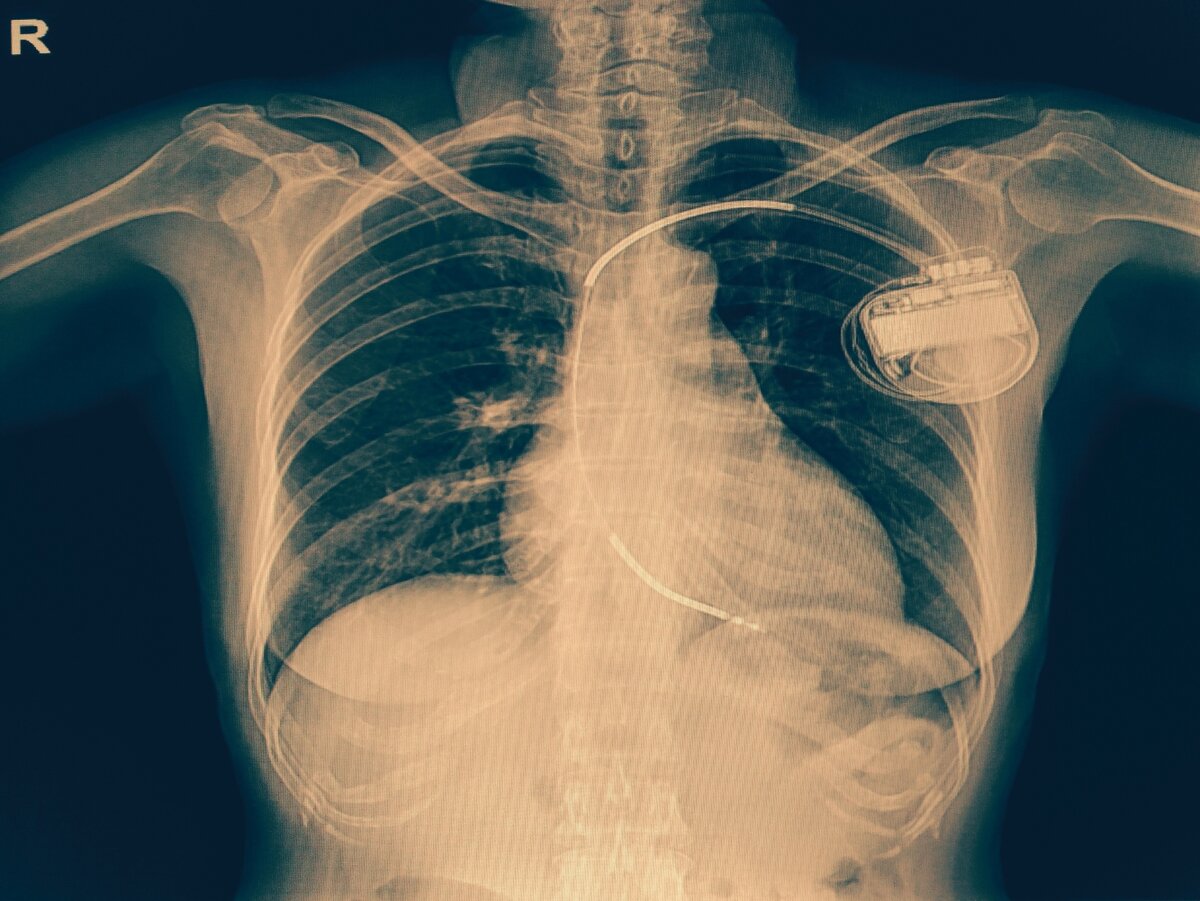

Имплантируемый кардиовертер-дефибриллятор (ИКД) - это кардиологическое устройство, используемое для лечения пациентов с нарушениями сердечного ритма (аритмией). ИКД вводится под мышцу на левой стороне грудной клетки и подключается к одному или двум проводам, которые ведут к сердцу через вену в верхней части грудной клетки.

Один из этих проводов подключается к нижней камере сердца (желудочку), а при необходимости второй – к в верхней камере (предсердию). Это устройство постоянно контролирует ваше сердце на предмет потенциально опасных сердечных ритмов. Если таковой обнаружен, ИКД посылает небольшой электрический разряд для восстановления нормального сердечного ритма.